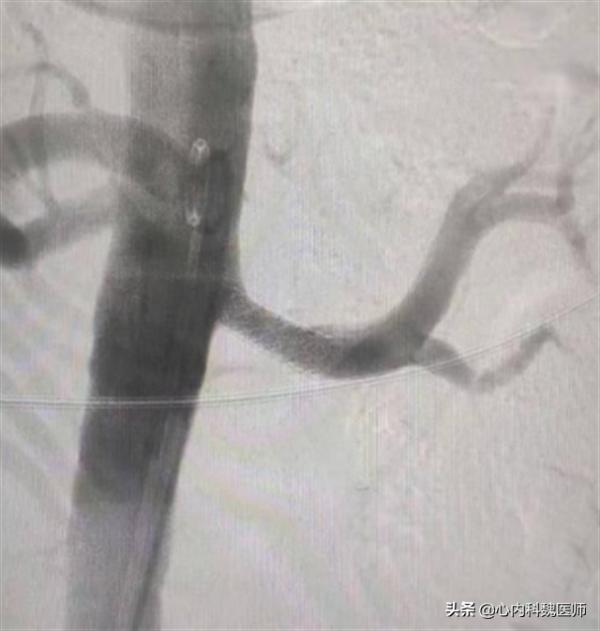

患者體溫36.7℃、血壓140/90、身高175cm、體重69kg,雙下肢重度凹陷性浮腫。尿常規提示尿蛋白2+,隱血2+,24小時尿蛋白定量9.820g,血肌酐210umol/L,腎部彩超雙腎大小:右96×54×50,左:103×52×56,提示腎囊腫、腹水。雙腎血管彩超結果提示腎動脈單側狹窄,腎穿刺病理示系膜增生性腎小球腎炎。可診斷為腎病綜合徵合併急性腎衰竭。